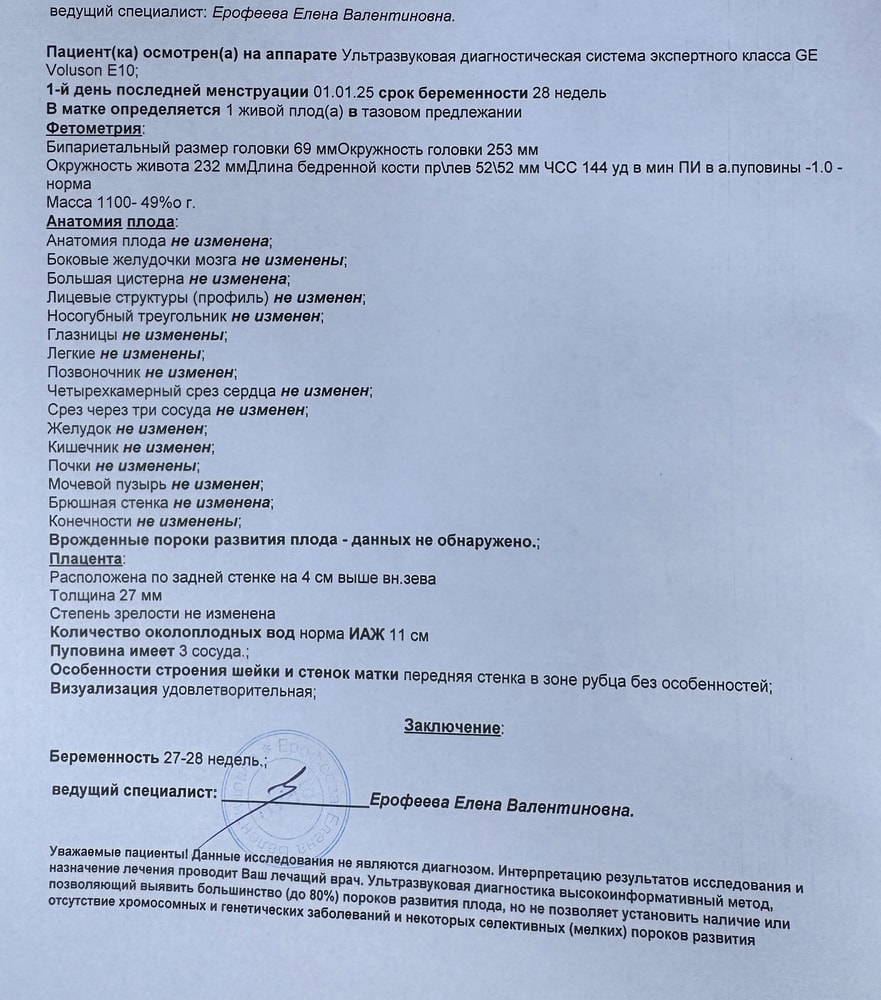

Девочки, привет! Сходила на узи 4D. Четкость конечно не очень… постоянно закрывала лицо ручками. Но самое главное - у ребенка все хорошо! Весим уже 1100 гр. Обязательно еще схожу!

Марина, четкости нет. Просто видно что ребеночек. Носик немного вздернут, как у мужа. Посмотрим какая родится😊

Марина, там на лице и руки и пуповина, поэтому все не четко видно

Марина, у некоторых очень даже хорошо видно лицо. У меня не очень получилось… Видимо качество еще такое, наверное в этой клинике оборудование не очень современное. Хотя деньги не малые берут. Смотрите отзывы